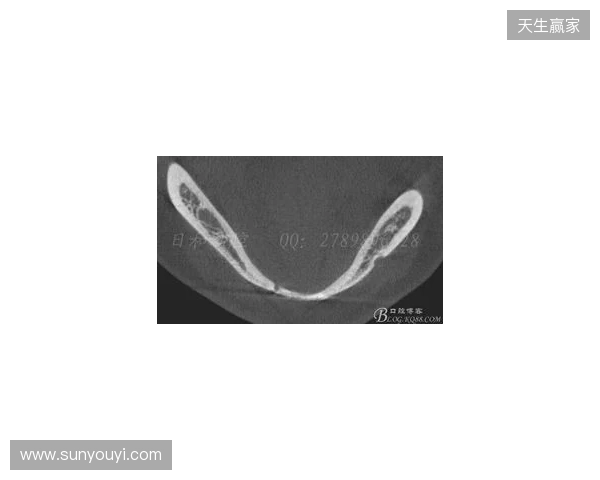

根据医院的检查结果,韦林顿·席尔瓦的上唇部受伤程度较为严重,属于贯通伤,已经进行了清创缝合。这种类型的伤势不仅影响外观,还可能对球员的饮食和发声造成影响。更为严重的是,他的上颌前牙区还出现了骨折,意味着席尔瓦在恢复期间将面临长时间的治疗和康复过程。

球员的第11和第21牙出现了半脱位的情况,这可能会导致他在恢复后需要进行进一步的牙科治疗,甚至有可能影响到他今后的职业生涯。医生表示,虽然通过手术和治疗可以恢复,但心理层面的恢复同样重要。